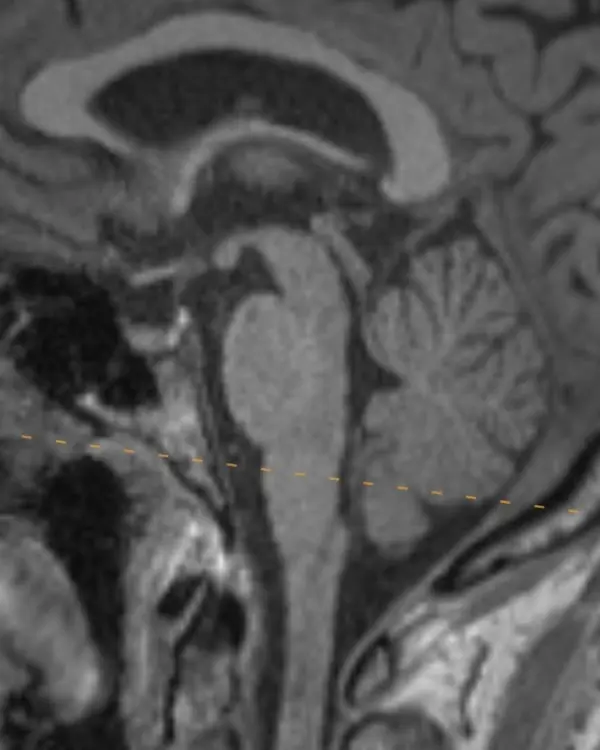

The brainstem, outlined in a white dotted line, is divided into the midbrain, pons, and medulla. Each segment has a characteristic appearance that is easiest to recognize in the sagittal plane.

Notice the beak-shaped anterior margin of the midbrain and the cerebrospinal fluid (CSF) space underneath it.

The pons has a bulbous contour anteriorly and a triangular shaped CSF space posterior to it.

The medulla is thin, gradually blends in appearance with the cervical spinal cord, and has a small CSF channel posterior to it.

Although easiest to see in the sagittal plane, these and some additional features that are unique to each division can be used to orient yourself in the axial plane.